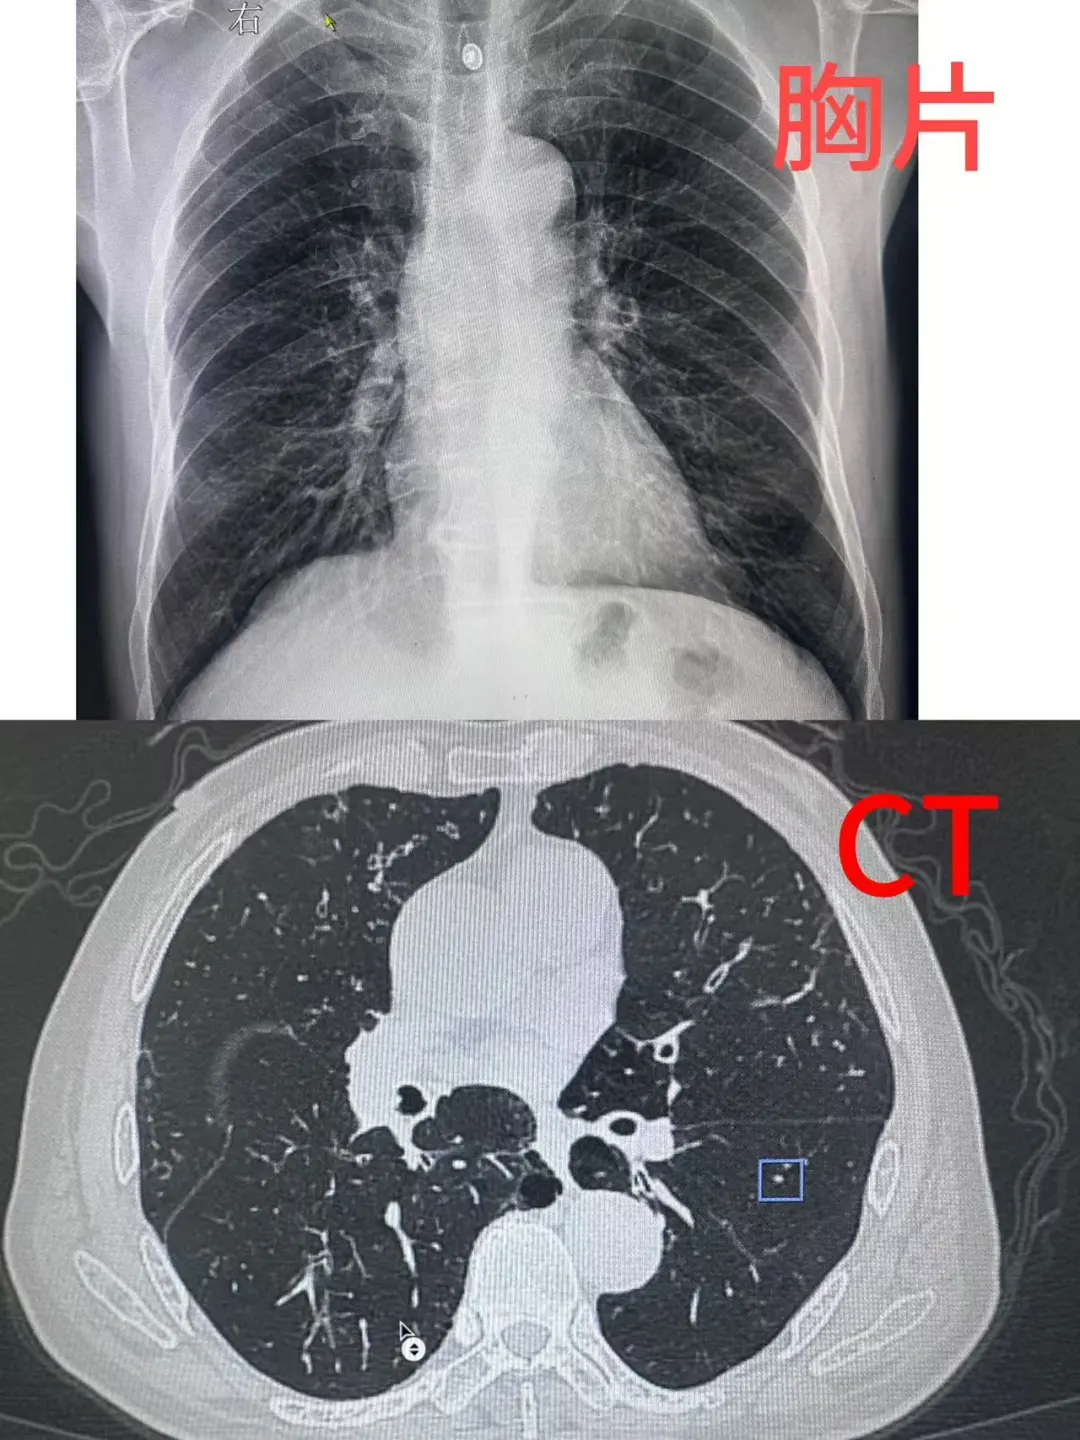

一、为什么查肺结节,CT比胸片更靠谱?

很多人疑惑,每年常规体检做了胸片,为何还会突然查出肺结节?答案很简单:胸片的“漏诊率”远高于CT。

胸片是胸部的平面成像,就像把立体的胸腔“压扁”成一张纸,心脏、肋骨、血管等结构会相互重叠遮挡。对于直径小于5毫米的微小结节,或位于肺尖、脊柱旁等隐蔽位置的结节,胸片很容易“视而不见”。而胸部CT采用断层扫描技术,能从不同角度、不同层面清晰显示肺部结构,哪怕是1-2毫米的微小病灶也能被精准捕捉,灵敏度是胸片的10倍以上。

更重要的是,低剂量螺旋CT已成为肺结节筛查的“金标准”——它的辐射剂量仅为常规CT的1/5-1/3,相当于1-2次胸片的辐射量,安全性高,适合作为40岁以上人群的年度筛查手段。对于长期吸烟、有肺癌家族史、接触粉尘或有害气体的高危人群,低剂量螺旋CT更是不可或缺的“健康卫士”。

曾遇到这样一位患者:一年前检查发现结节大小14mm,时隔一年复查,CT显示原结节已增大至27.5mm,且出现分叶、毛刺等恶性特征,穿刺活检确诊为右下肺腺癌。

这个病例恰恰说明:即使是看似“安全”的微小结节,也不能掉以轻心。规范随访不是过度检查,而是用最低的成本守住健康底线。如果这位患者能按时复查,在结节刚出现形态变化时就干预,治疗效果和预后都会好得多。